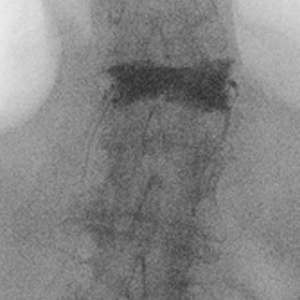

Spinal stenosis (Lumbar) Spinal stenosis (Cervical) Spinal stenosis (Thoracic) Lumbar Disc Herniation Spondylolisthesis Cervical Foraminal Stenosis Vertebroplasty Lumbar Fusion Anterior Cervical Fusion (ACDF) Posterior Cervical Fusion Thoracic Fusion Revision Lumbar Fusion Surgery Facet Joint Cyst Spinal Tumour Minimally Invasive Lumbar Fusion (XLIF) Minimally Invasive Lumbar Fusion (ALIF) Lumbar Fusion (TLIF) Thoraco-lumbar Fusion Lumbar Corpectomy Complex Lumbar Spine Surgery (Spino-pelvic fixation) Complex Cervical Spine Surgery Complex Thoracic Spine Surgery Occipito-cervical Fusion Minimally invasive surgery for thoracic disc herniation Other Related Topics